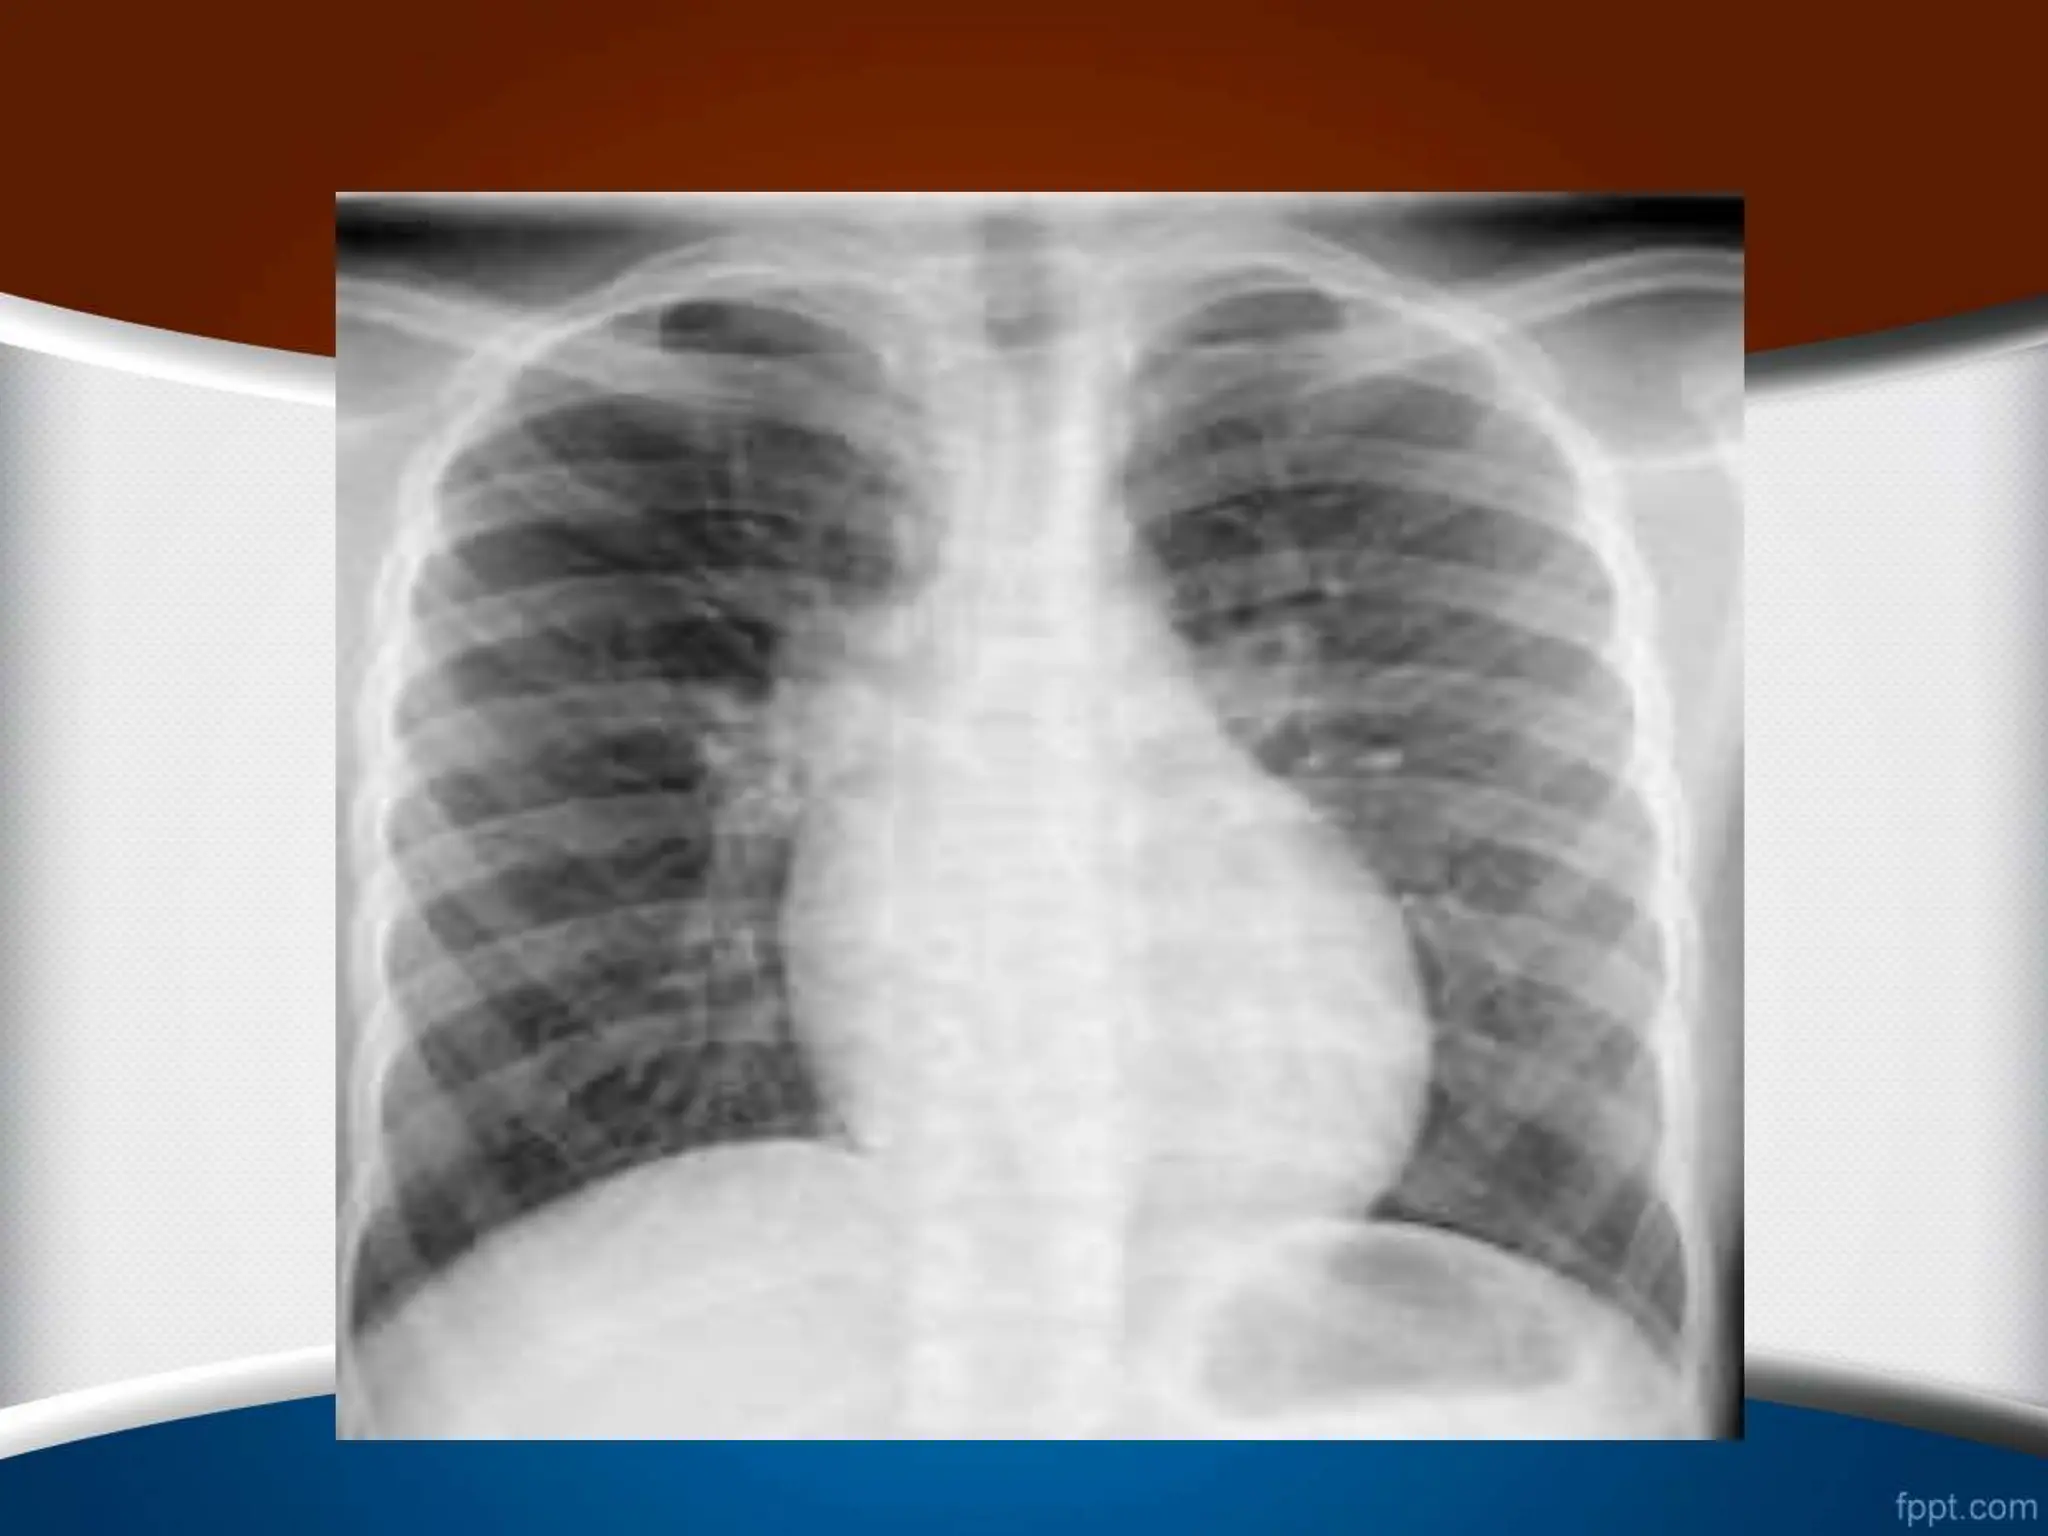

‫راست‬ ‫بطن‬ ‫بزرگی‬

‫گرافی‬ ‫در‬ ‫هم‬ ‫مورد‬ ‫این‬ ‫در‬

PA

‫نوک‬ ‫شدن‬ ‫گرد‬ ‫سینه‬ ‫قفسه‬

‫دی‬ ‫دیافراگم‬ ‫باالی‬ ‫طرف‬ ‫به‬ ‫آن‬ ‫جایی‬ ‫جابه‬ ‫با‬ ‫همراه‬ ‫قلب‬

‫ده‬

‫شود‬ ‫می‬

.

•

ً‫ال‬‫معمو‬ ‫راست‬ ‫بطن‬ ‫شدید‬ ‫بزرگی‬ ‫در‬

CTR

‫یافته‬ ‫افزایش‬

‫است‬